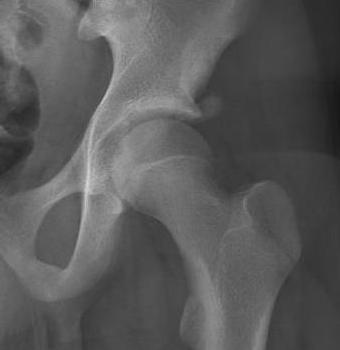

ASIS Avulsion

Attachments

Sartorius & Tensor fascia lata

Imaging

ASIS displaced 1ASIS displaced 2